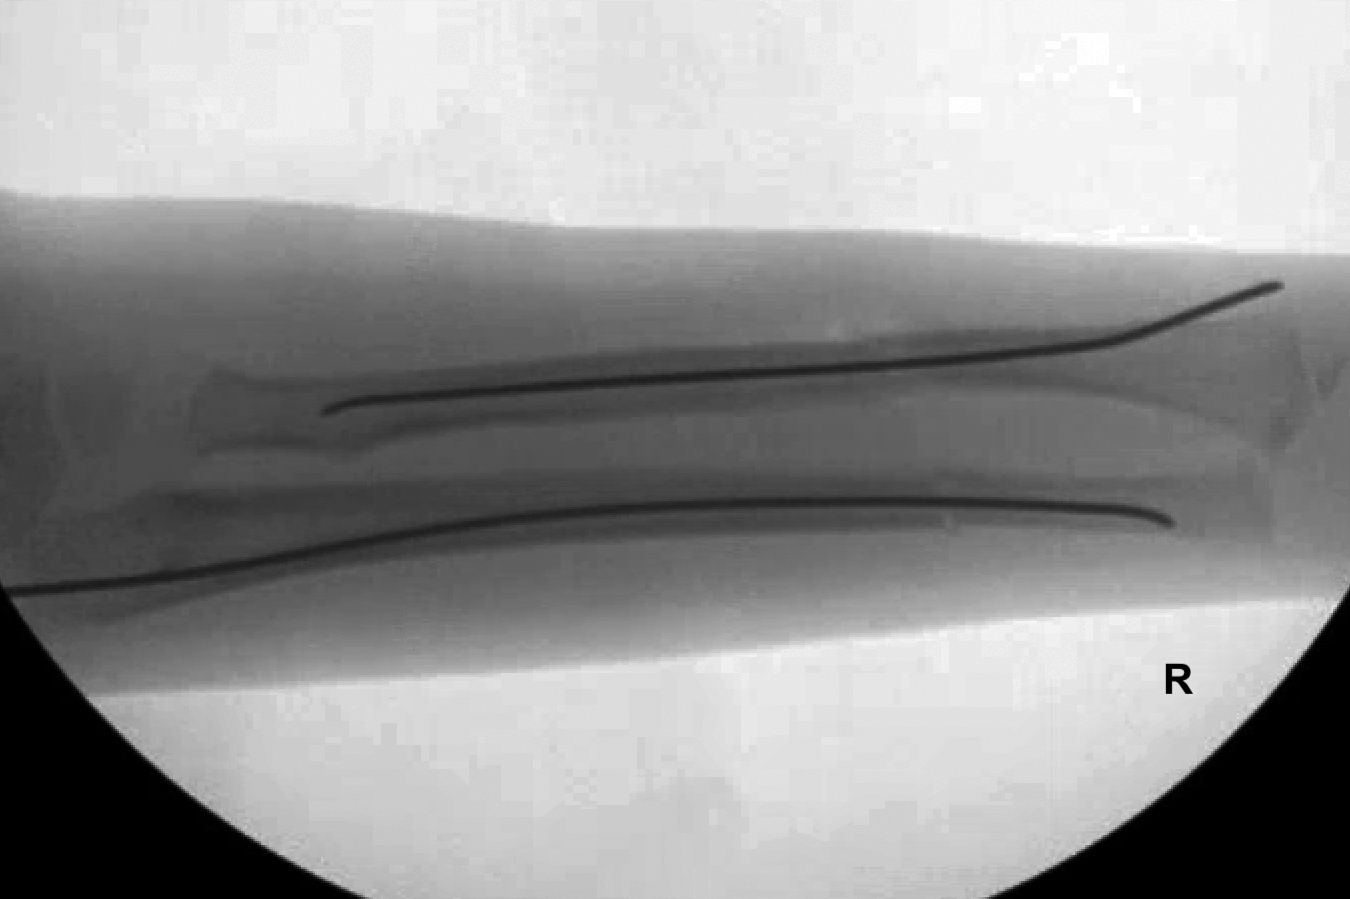

- Titanium elastic intramedullary nail fixation is recommended for short, oblique fractures.

- Open reduction and internal fixation (ORIF) with plates and screws is recommended for comminuted or long oblique ulna fractures.17